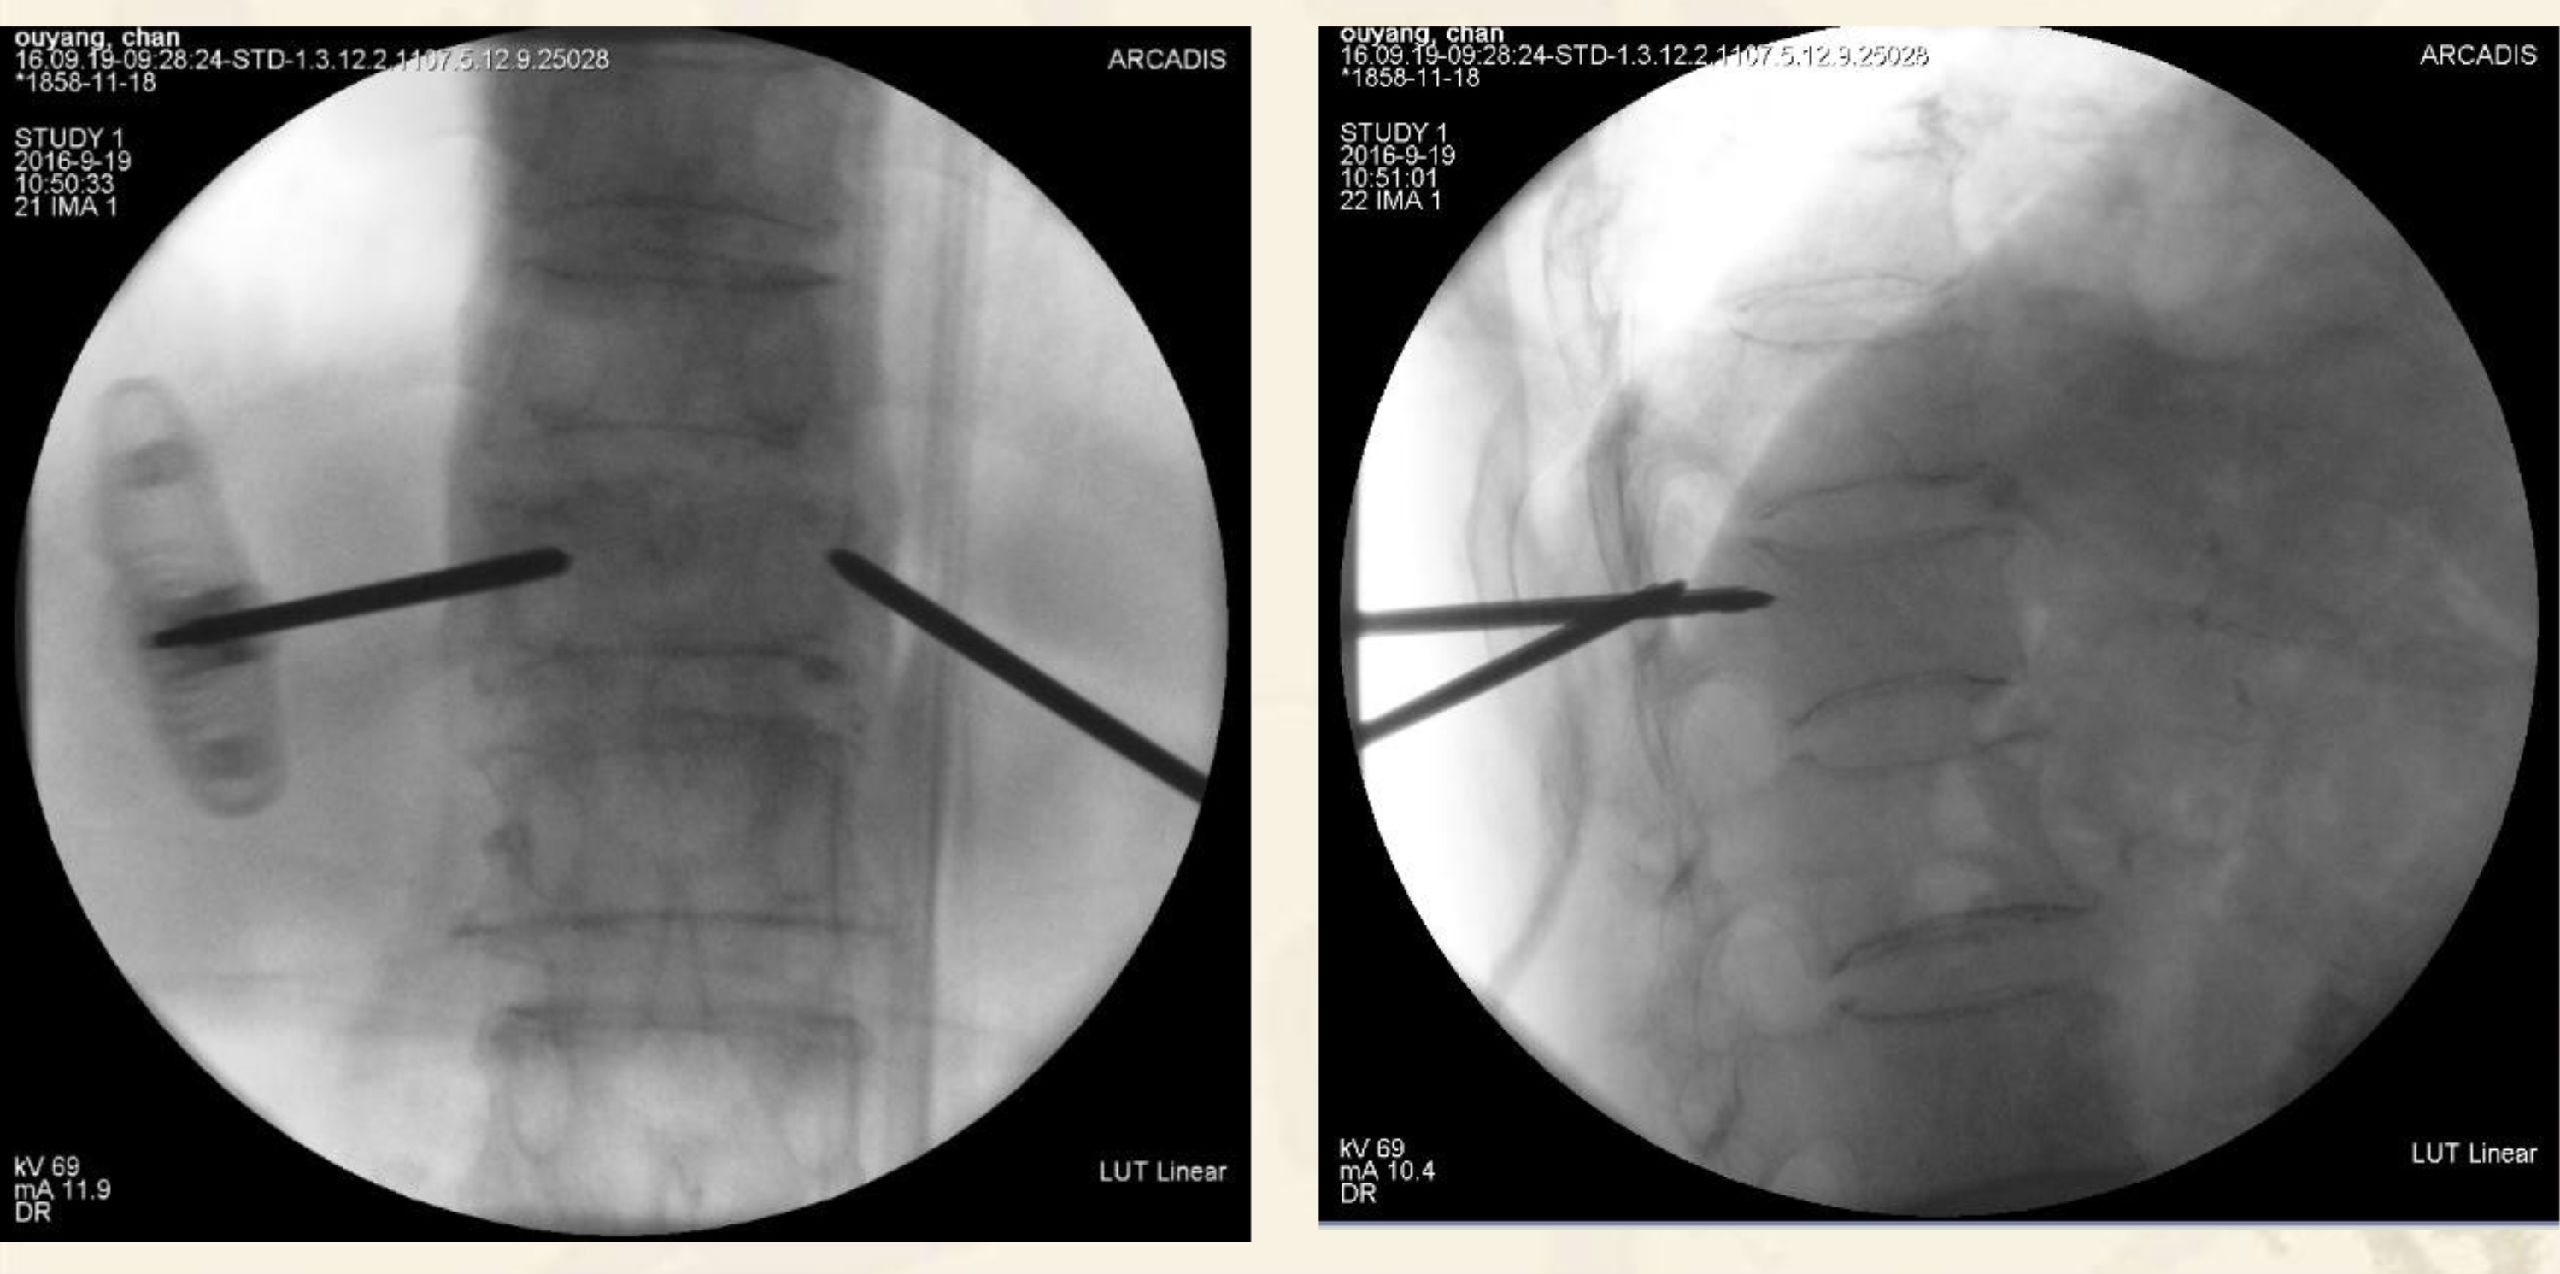

术中透视图

透视引导下,经椎弓根入路或根旁

靶向骨折区置管

侧开口推杆控制骨水泥弥散方向